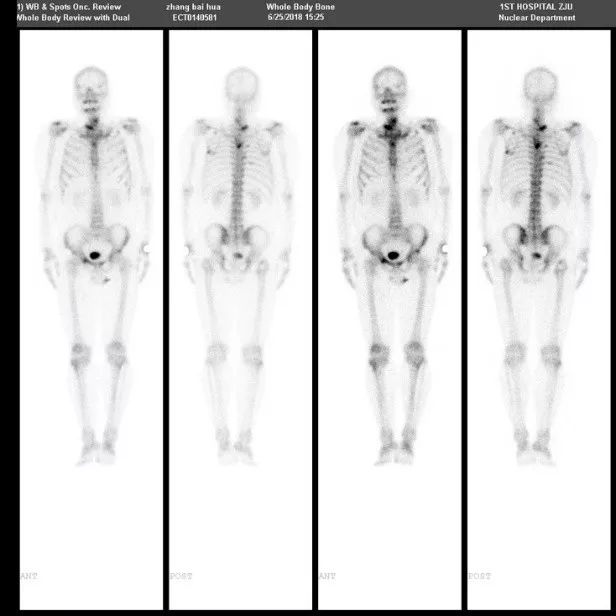

ECT

2018.6.25:颈椎下段,右侧肩胛骨,右侧第1肋,胸4椎体,右侧5、8后肋,左侧骶髂关节,右侧髋关节,右侧耻骨骨质代谢局灶性活跃,首先考虑骨转移。

2018.11.21:上述骨骼代谢局灶性活跃,多数病灶较前代谢降低。